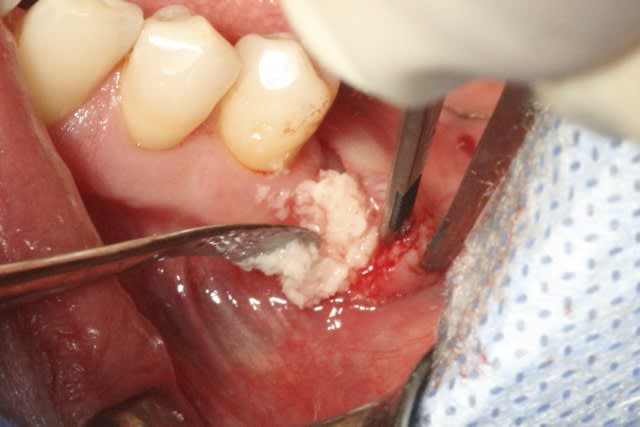

image 5: broyât osseux

image8: ajout du broyât

Désolé pour la qualité, c'est tout ce que j'ai..